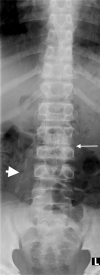

Tuberculosis (TB) remains one of the major public health threats worldwide, despite improved diagnostic and therapeutic methods. Tuberculosis is one of the main causes of infectious disease in the chest and is associated with substantial morbidity and mortality in paediatric populations, particularly in low- and middle-income countries. Due to the difficulty in obtaining microbiological confirmation of pulmonary TB in children, diagnosis often relies on a combination of clinical and radiological findings. The early diagnosis of central nervous system TB is challenging with presumptive diagnosis heavily reliant on imaging. Brain infection can present as a diffuse exudative basal leptomeningitis or as localised disease (tuberculoma, abscess, cerebritis). Spinal TB may present as radiculomyelitis, spinal tuberculoma or abscess or epidural phlegmon. Musculoskeletal manifestation accounts for 10% of extrapulmonary presentations but is easily overlooked with its insidious clinical course and non-specific imaging findings. Common musculoskeletal manifestations of TB include spondylitis, arthritis and osteomyelitis, while tenosynovitis and bursitis are less common. Abdominal TB presents with a triad of pain, fever and weight loss. Abdominal TB may occur in various forms, as tuberculous lymphadenopathy or peritoneal, gastrointestinal or visceral TB. Chest radiographs should be performed, as approximately 15% to 25% of children with abdominal TB have concomitant pulmonary infection. Urogenital TB is rare in children. This article will review the classic radiological findings in childhood TB in each of the major systems in order of clinical prevalence, namely chest, central nervous system, spine, musculoskeletal, abdomen and genitourinary system.